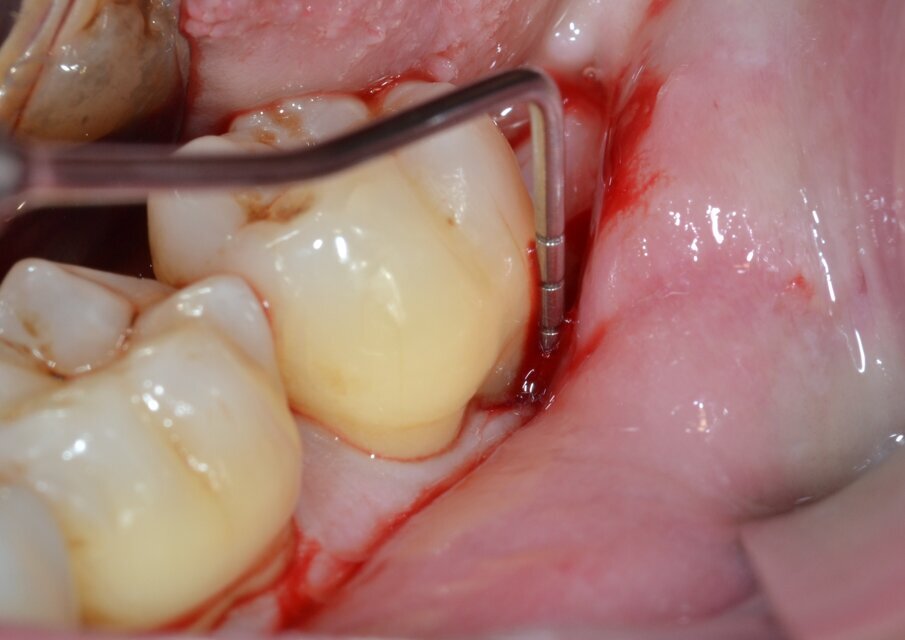

Dopo analgesia locale ottenuta per infiltrazione di Articaina cloridrato 40 mg con epinefrina 1:100.000 viene effettuata l’incisione di accesso secondo la tecnica denominata “Crestal Incision”4 per elevare un lembo a spessore totale che espone l’area interessata dal difetto (Fig. 5). Il debridement e la decontaminazione della superficie radicolare vengono effettuati per mezzo di inserti ultrasonici dedicati (Figg. 6, 7); al completamento di questo tempo chirurgico il difetto è innestato con biomateriale eterologo protetto da una membrana di tipo riassorbibile in pericardio di origine animale che viene fissata sulla cresta ossea mediante pins in titanio allo scopo di stabilizzare il coagulo e guidare la rigenerazione tissutale all’ interno del difetto. La ferita chirurgica è suturata con un filo riassorbibile 6/0 in PGA (Figg. 8-12).

Fig. 7 - Debridement del difetto intraosseo e decontaminazione della superficie radicolare mediante ultrasuoni (aspetto distale).